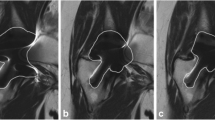

a. A 27 year - old female received a distal femoral endoprosthetic reconstruction after wide resection of an osteosarcoma 6 years prior to the exmaination. b. Conventional STIR image and c. MAVRIC image were compared for the depiction of surrounding soft tissue adjacent to the endoprosthesis. Joint effusion is observed surrounding the metal implant in MAVRIC image (red arrow). Due to early detection of the periprosthetic infection, thorough irrigation and debriedement was performed, and the patient is well without recurrence